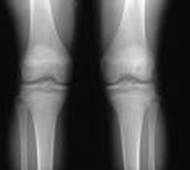

Radiografia genunchi bilateral A-P

Radiografia genunchiului - A-P

Pacientul in DD; gamba in extensie piciorul perpendicular pe masa.

RC perpendiculara pe caseta; intra la un lat de deget sub varful rotulei. Film de 18x24 cm, in lung; marginea proximala a casetei la un lat de mana deasupra rotulei; marginea mediala si cea laterala la egala distanta de partile moi.

Distanta F-F = 1m, fara Bk.